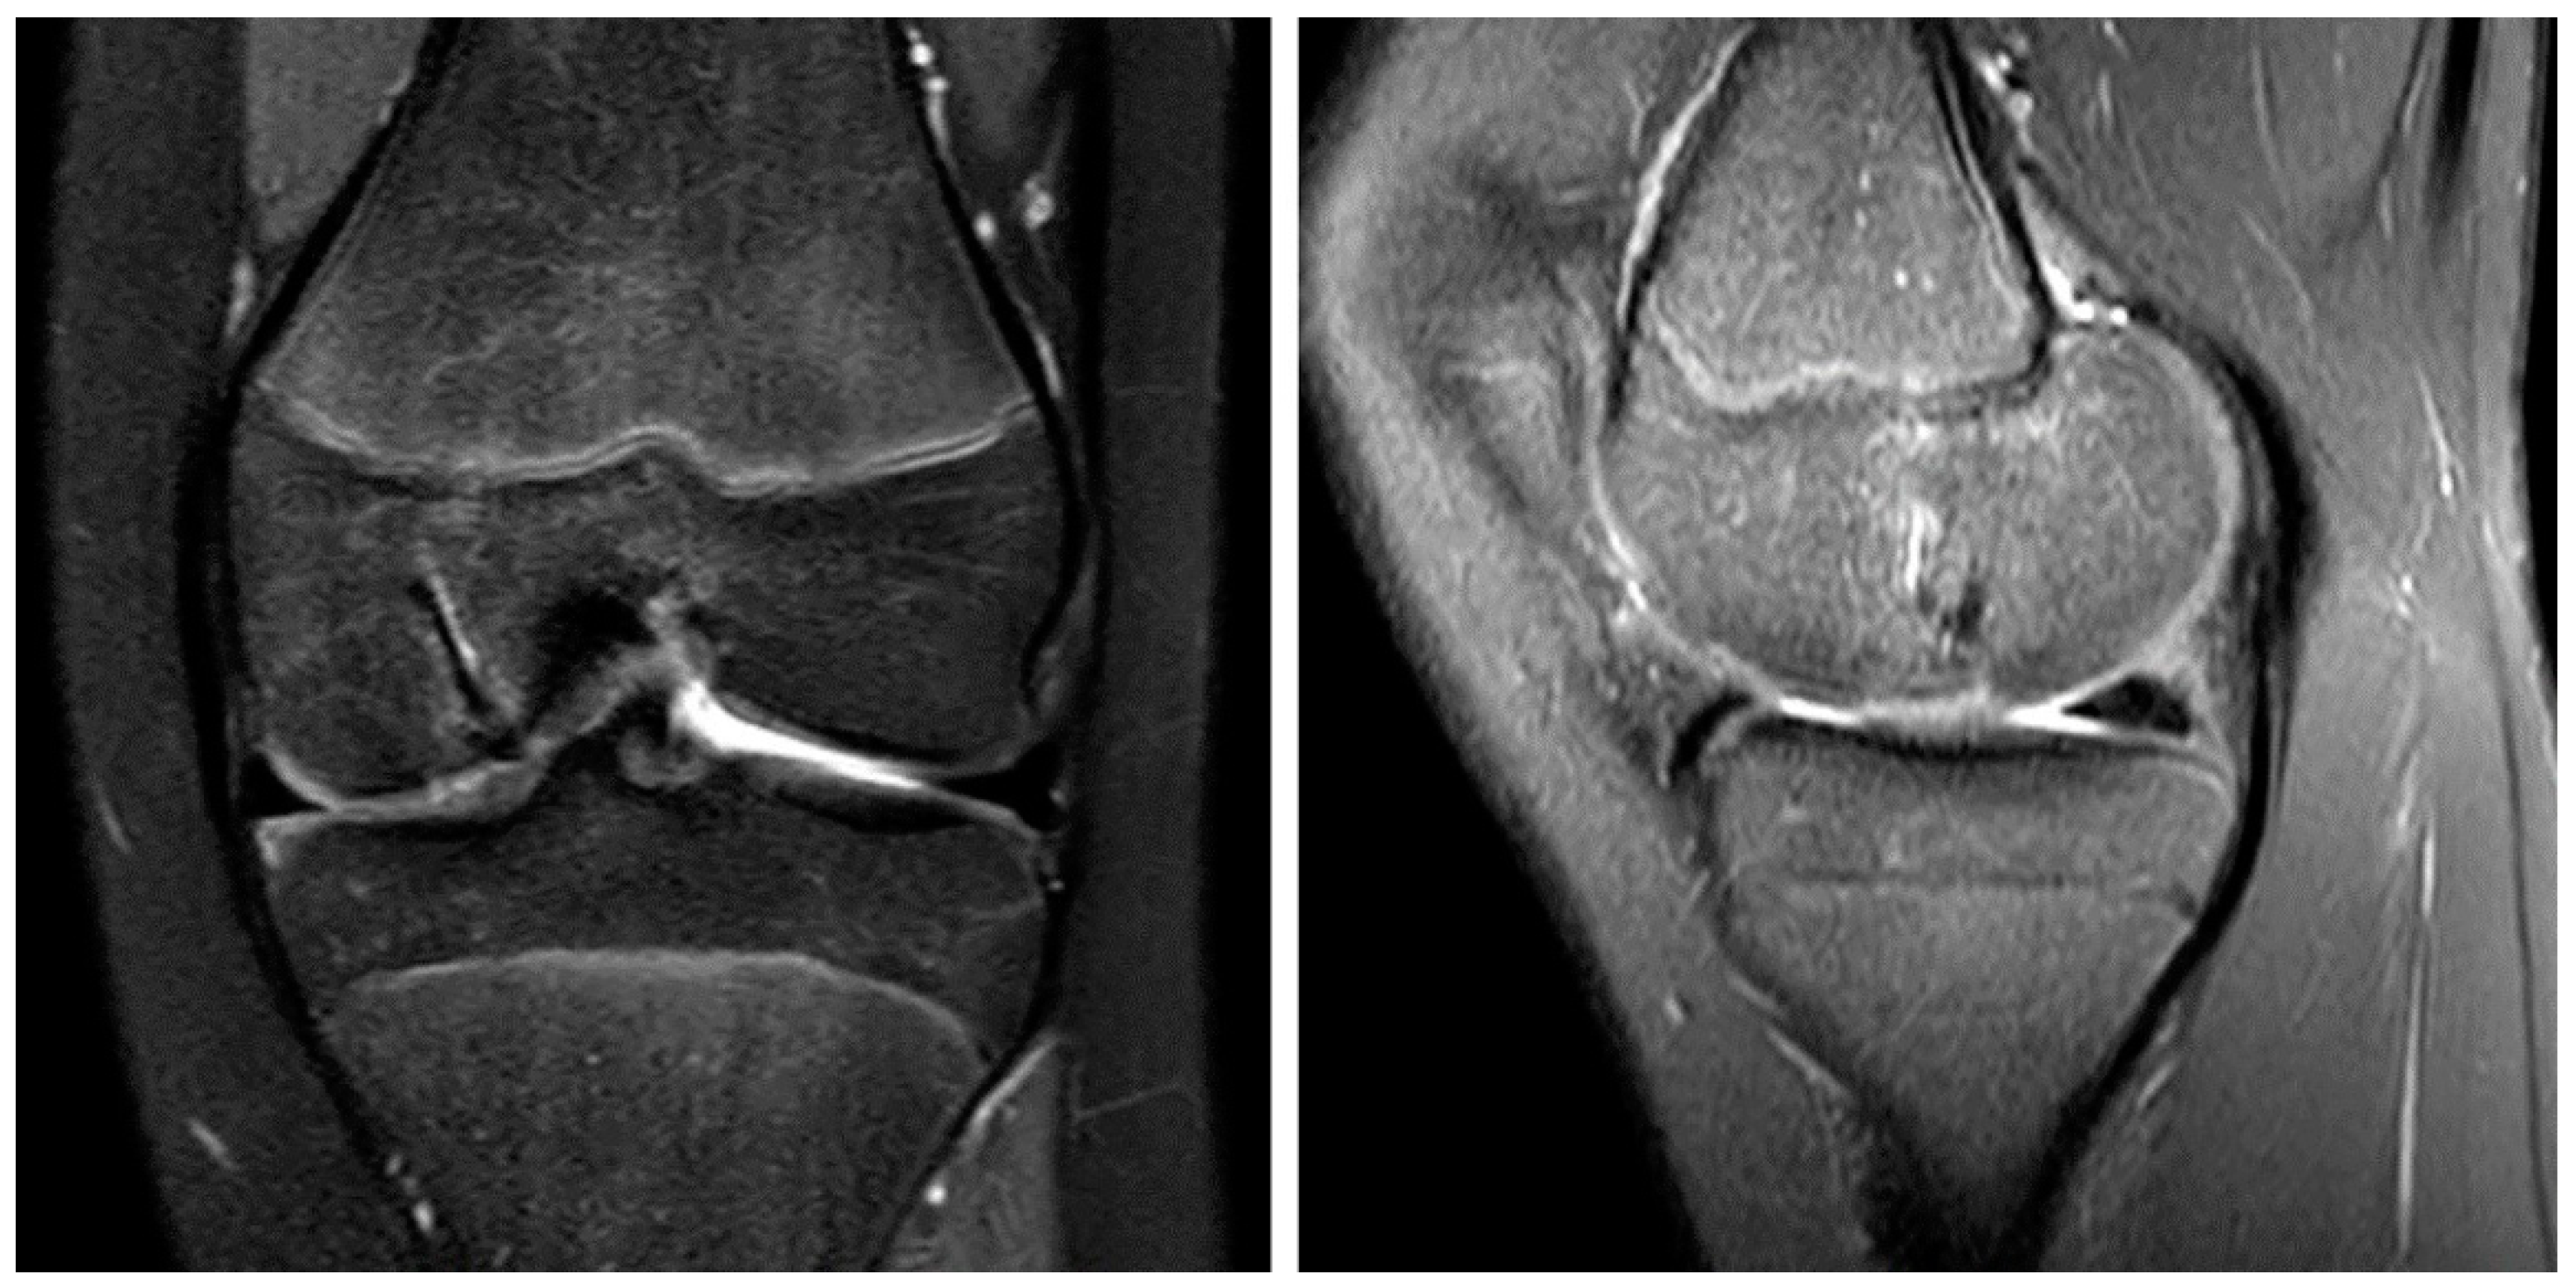

2. Case Report